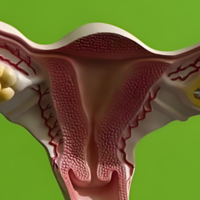

存在卵巢过早衰老、多囊卵巢综合征,以及肾上腺皮质功能、甲状腺皮质功能,以及脑垂体功能、下丘脑脑功能等异样的病人,卵巢中卵泡数目就会数量少。对在这方面片面患者是可以做试管婴儿促排的,终究卵泡数量未几会导致自然怀孕成功率降低,而试管婴儿促排的目的就是使用药物刺激女性卵巢,以增加卵巢中卵泡的数目,从而提升受孕概率。其次试管婴儿促排还能促使女性卵巢中多个卵泡相继成长发育,直至发育成熟即B超监测下卵泡大小在18-22mm之间,进而就能够取出多个成熟卵泡用于与精子进行受精,进而提高怀孕概率。